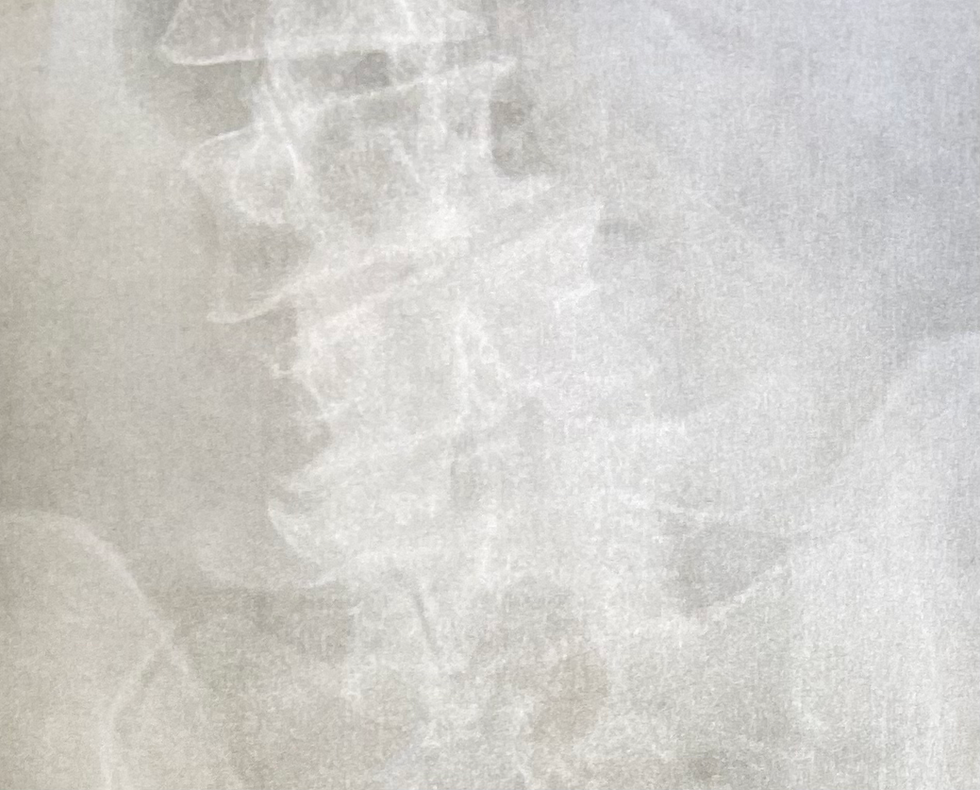

When I saw my x-ray, I gasped and said, "Oh shit." I've seen lots of x-rays of my back, but none of them looked this bad. It was like my arthritis had been on steroids and my scoliosis looked much worse.

The x-ray showed endplate degenerative changes in the lumbar spine. There were osteophytes (bone spurs) at the ends of three of my vertebrae. That was new.

After showing me the picture of my sad back, the North Platte APRN said, "You're too young for back surgery or lifelong injections, so physical therapy (PT)?"